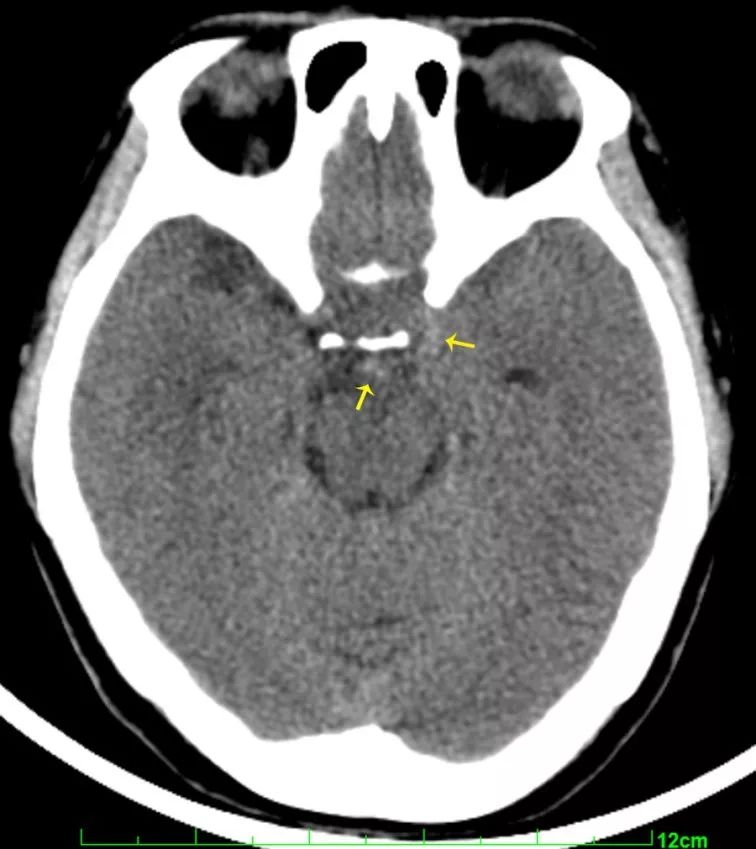

左侧颈内动脉后交通段动脉瘤;诊断:辅助检查:头颅cta示"左侧颈内动脉

图1 入院后ct平扫提示前纵裂蛛网膜下腔出血cta提示:前交通动脉瘤.